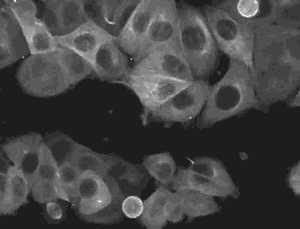

脐带间充质干细胞体外显示有很高的分化能力,可分化成软骨细胞、脂肪细胞、成骨细胞、成牙本质样细胞、真皮成纤维细胞、平滑肌细胞、骨骼细胞、心肌细胞、肝细胞,产生胰高血糖素细胞、生长抑素分泌细胞、神经胶质细胞(少突胶质细胞)和多巴胺能神经元等。

那么什么是间充质干细胞呢?间充质干细胞是干细胞家族的成员,具有自我复制能力和强大分化潜能。同时,间充质干细胞拥有其他干细胞所没有的优点,那就是它还具有向损伤组织定向迁移并根据具体环境来调节免疫反应的能力,这使其在临床应用上表现了巨大的潜力。

脐带间充质干细胞是来源于新生儿脐带组织,具有取材方便,无道德伦理争议,可获取的细胞数量多、增殖能力强、免疫调节作用大,分泌细胞生长因子的总量也非常高,便于扩增和传代,同时又没有配型、排异等优势,极其适合用于临床研究和应用,是间充质干细胞的理想来源。